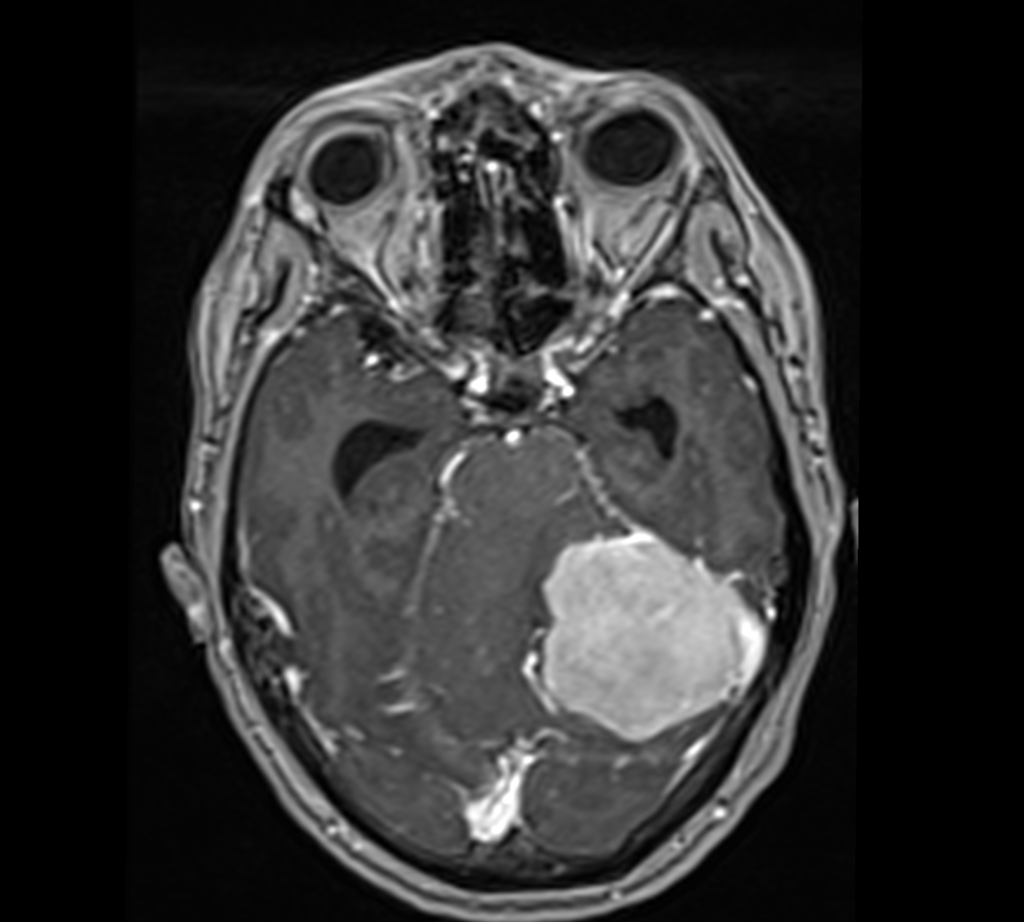

Tumores cerebrales

Gliomas hemisféricos, meningiomas, o schwanomas son algunos tumores que pueden asentar en el cráneo.

Producen una constelación de síntomas, y su diagnóstico exige de la realización de una resonancia magnética.

Algunos de ellos se localizan en la corteza cerebral, pero no es infrecuente otras localizaciones como la base del cráneo.